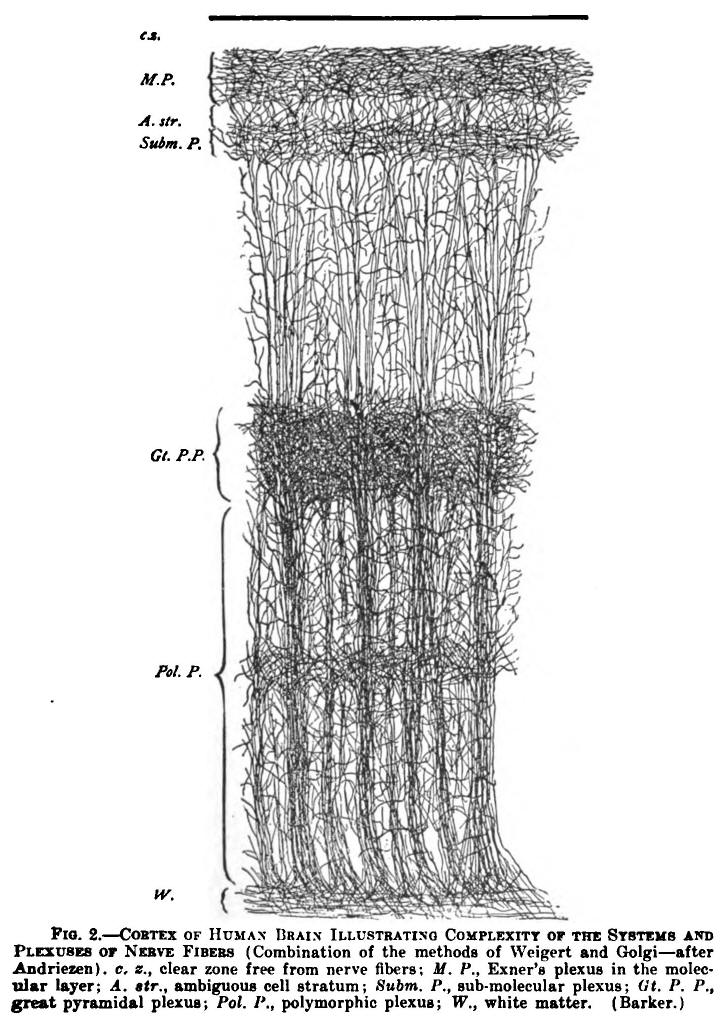

| 2. | Cortex of human brain illustrating complexity of the systems and plexuses of nerve fibers | 109 |